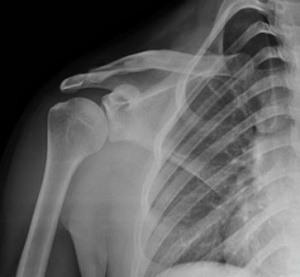

Рис. 7. Результат остеосинтеза перелома мыщелка плечевой кости: А — рентгенограмма до операции; B — рентгенограмма после операции